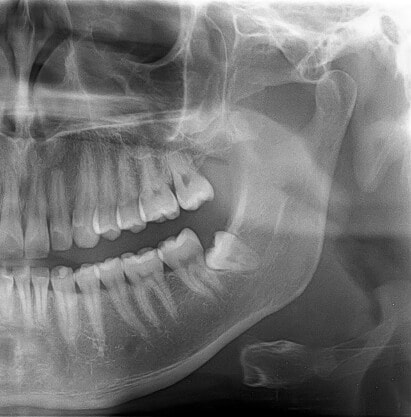

Das in der Praxisklinik Herne eingesetzte digitale Röntgen ist der konventionellen Röntgenmethode mit Filmen haushoch überlegen. Auf den kontrastreichen digitalen Röntgenbildern werden auch kleinste Details Ihres Kauapparates abgebildet. So lassen sich auf ihnen beispielsweise erste Anzeichen für Entzündungserkrankungen und einen Knochenabbau erkennen. Außerdem ist die Strahlenbelastung beim digitalen Röntgen um sage und schreibe 90% geringer als bei der herkömmlichen Röntgenmethode. Mehr über digitales Röntgen in der Praxisklinik Herne erfahren.

Röntgen mit DVT (Digitaler Volumentomograph) ist das Pendant in 3D zum digitalen 2D-Röntgen. 3D-Röntgen hat die Zahndiagnostik in Herne und insbesondere die Implantologie revolutioniert, denn sie ermöglicht die exakte räumliche Beurteilung und Vermessung des Kauapparates. Sie gibt nicht nur Auskunft über das noch vorhandene Knochenangebot, sondern auch über die Zahnstellung sowie die Lage von Kieferhöhlen und Nervenbahnen. Die Ergebnisse der 3D-Diagnostik ermöglichen die Planung der idealen Implantatpositionen unter Ausnutzung des vorhandenen Knochens und unter Umgehung sensibler Strukturen. 3D-(DVT-) Aufnahmen bilden somit die Grundlage für die minimalinvasive Implantologie und verringern das Risiko für Behandlungsfehler. Zu tief oder niedrig gesetzte Implantate, sowie Implantate in falschen Abständen zu benachbarten Strukturen/Zähnen gehören somit der Vergangenheit an. Voraussetzung hierfür ist, dass die Ergebnisse der DVT-Zahndiagnostik von einem entsprechend ausgebildeten und erfahrenen Experten für Implantologie interpretiert wird. Mehr über die DVT-Zahndiagnostik in der Praxisklinik Herne erfahren.

Der Volumentomograph bietet derzeit die genauste 3D-Untersuchungsmöglichkeit bei einer deutlich geringeren Strahlenbelastung gegenüber den bekannten traditionellen Computertomographie. Er erzeugt Schnittbilder des Schädels, womit die Fehlstellungen schneller und eindeutiger gesehen werden können.